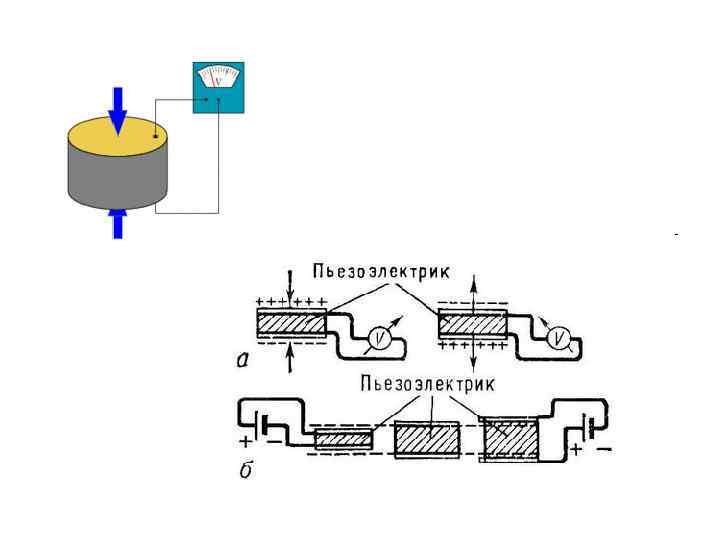

• Прямой эффект открыт братьями Жаком и Пьером Кюри в 1880 г. • Обратный эффект был предугадан в 1881 г. Липпманом на основе термодинамических соображений и в том же году экспериментально подтверждён братьями Кюри.

• Прямой эффект открыт братьями Жаком и Пьером Кюри в 1880 г. • Обратный эффект был предугадан в 1881 г. Липпманом на основе термодинамических соображений и в том же году экспериментально подтверждён братьями Кюри.

• Получение ультразвуковых волн базируется на обратном пьезоэлектрическом эффекте • Детектирование отраженных ультразвуковых сигналов базируется на прямом пьезоэлектрическом эффекте

• Получение ультразвуковых волн базируется на обратном пьезоэлектрическом эффекте • Детектирование отраженных ультразвуковых сигналов базируется на прямом пьезоэлектрическом эффекте